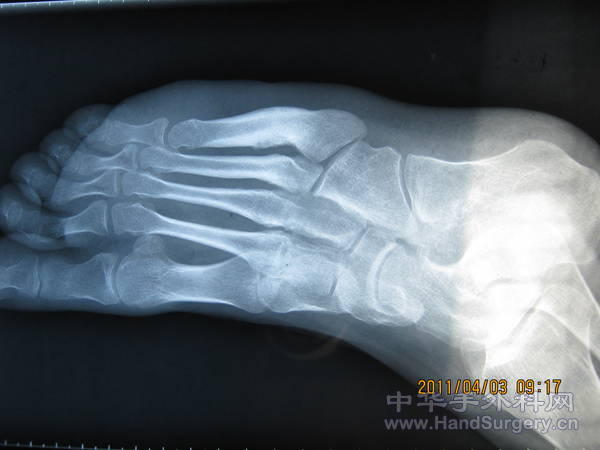

一例神经损伤引起的马蹄内翻足的术前术后

补充:DR片是术前拍的。昨天来复查,走路基本正常了,就是踝关节活动幅度较健侧小。复查是术后三月。

本例是

1.充分松解侧各关节韧带。

2.Z字延长跟腱。远端保留腓侧。近端保留胫侧。

3.将胫前肌腱自止点剥离转位至外侧楔骨电钻打眼重建止点。

4.内侧皮肤缺损家属不愿做皮瓣或植皮。最后一个月换药愈合。

提醒:手术方案依神经可支配肌肉肌力而定。每例手术都不一样。不要照搬。要具体问题具体分析。

很好,假如是先天性马蹄内翻足,这么大的年龄将会有骨骼发育畸形,。。。矫正后会出现创伤性骨性关节炎;而此例是因为神经损伤引发的马蹄内翻足,骨性关节没有明显畸形,术后效果较好,一般不会发生骨性关节炎。